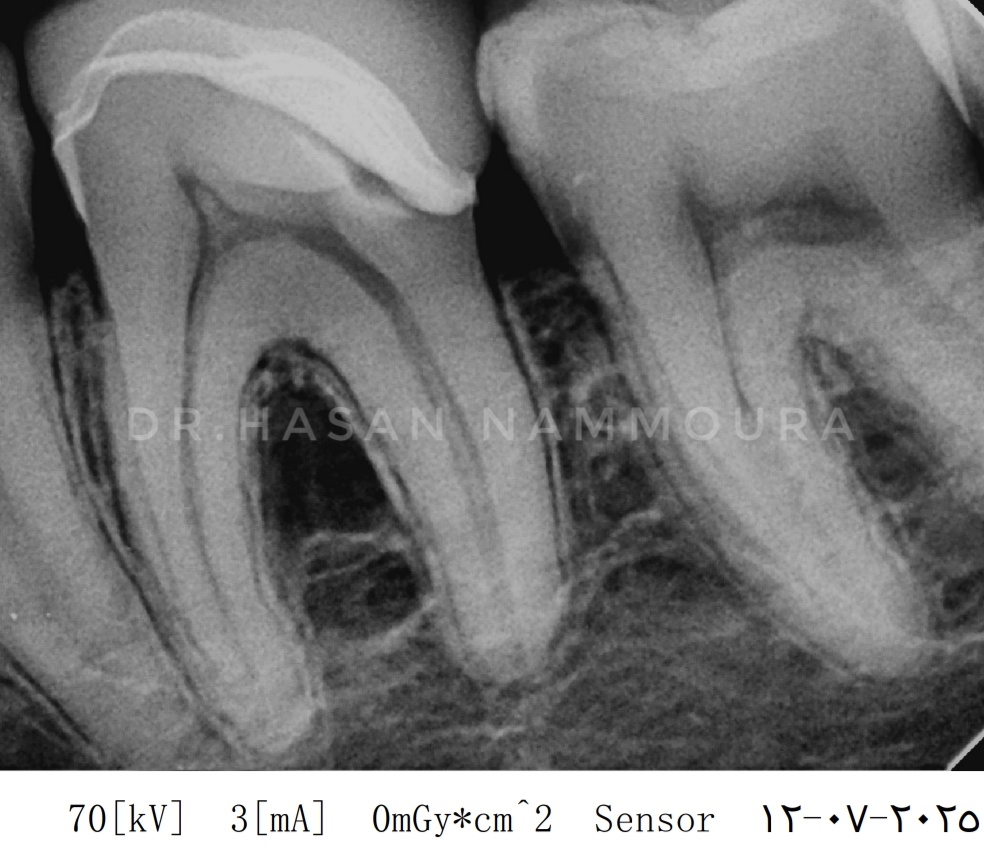

Post-treatment, the tooth remained vital and asymptomatic. Follow-up at 1, 3, and 6 years confirmed continued vitality, normal periapical structures, and no restoration failure. The 6-year radiograph showed no signs of pathology, with stable margins and no resorption.